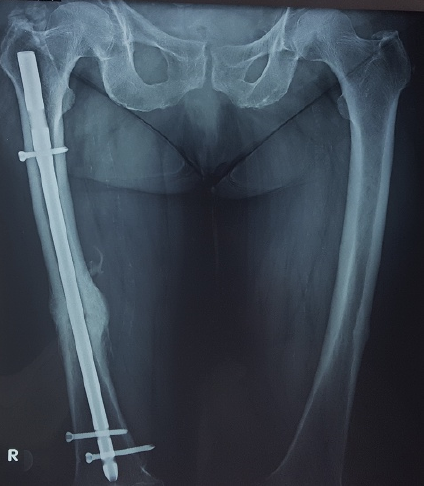

Patient’s medical history comprises hypertension, carotid stenosis, dyslipidemia, appendectomy, cholecystectomy andhysterectomy. The patient undergoes therapy with alendronate for six years due to osteoporosis. The patient also reports occasional feeling of heaviness in the left thigh over the past 2 years. This information from her medical history combined with the typical morphology of the fracture (noncomminuted transverse fracture of the femoral shaft), led the diagnostic approach to radiological investigation of the left femur too. The radiological examination revealed incomplete atypical fracture of the left femoral shaft with increased thickness of the lateral cortex (Figure 1).

Figure 1. AP radiographs of both femurs. The radiograph of the right femoral shaft shows a complete atypical femoral fracture. The radiograph of the left femoral shaft shows an incomplete atypical femoral fracture with increased thickness of the lateral cortex associated with a radiolucent horizontal line